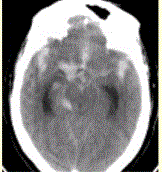

问题 患者男,50岁,突发昏迷、呕吐1h。查体:颈项强直,脑膜刺激征阳性,CT表现如图1。 初步诊断应为

选项 A.脑血肿 B.脑梗死 C.蛛网膜下腔出血 D.脑血管动静脉畸形 E.正常

答案 C